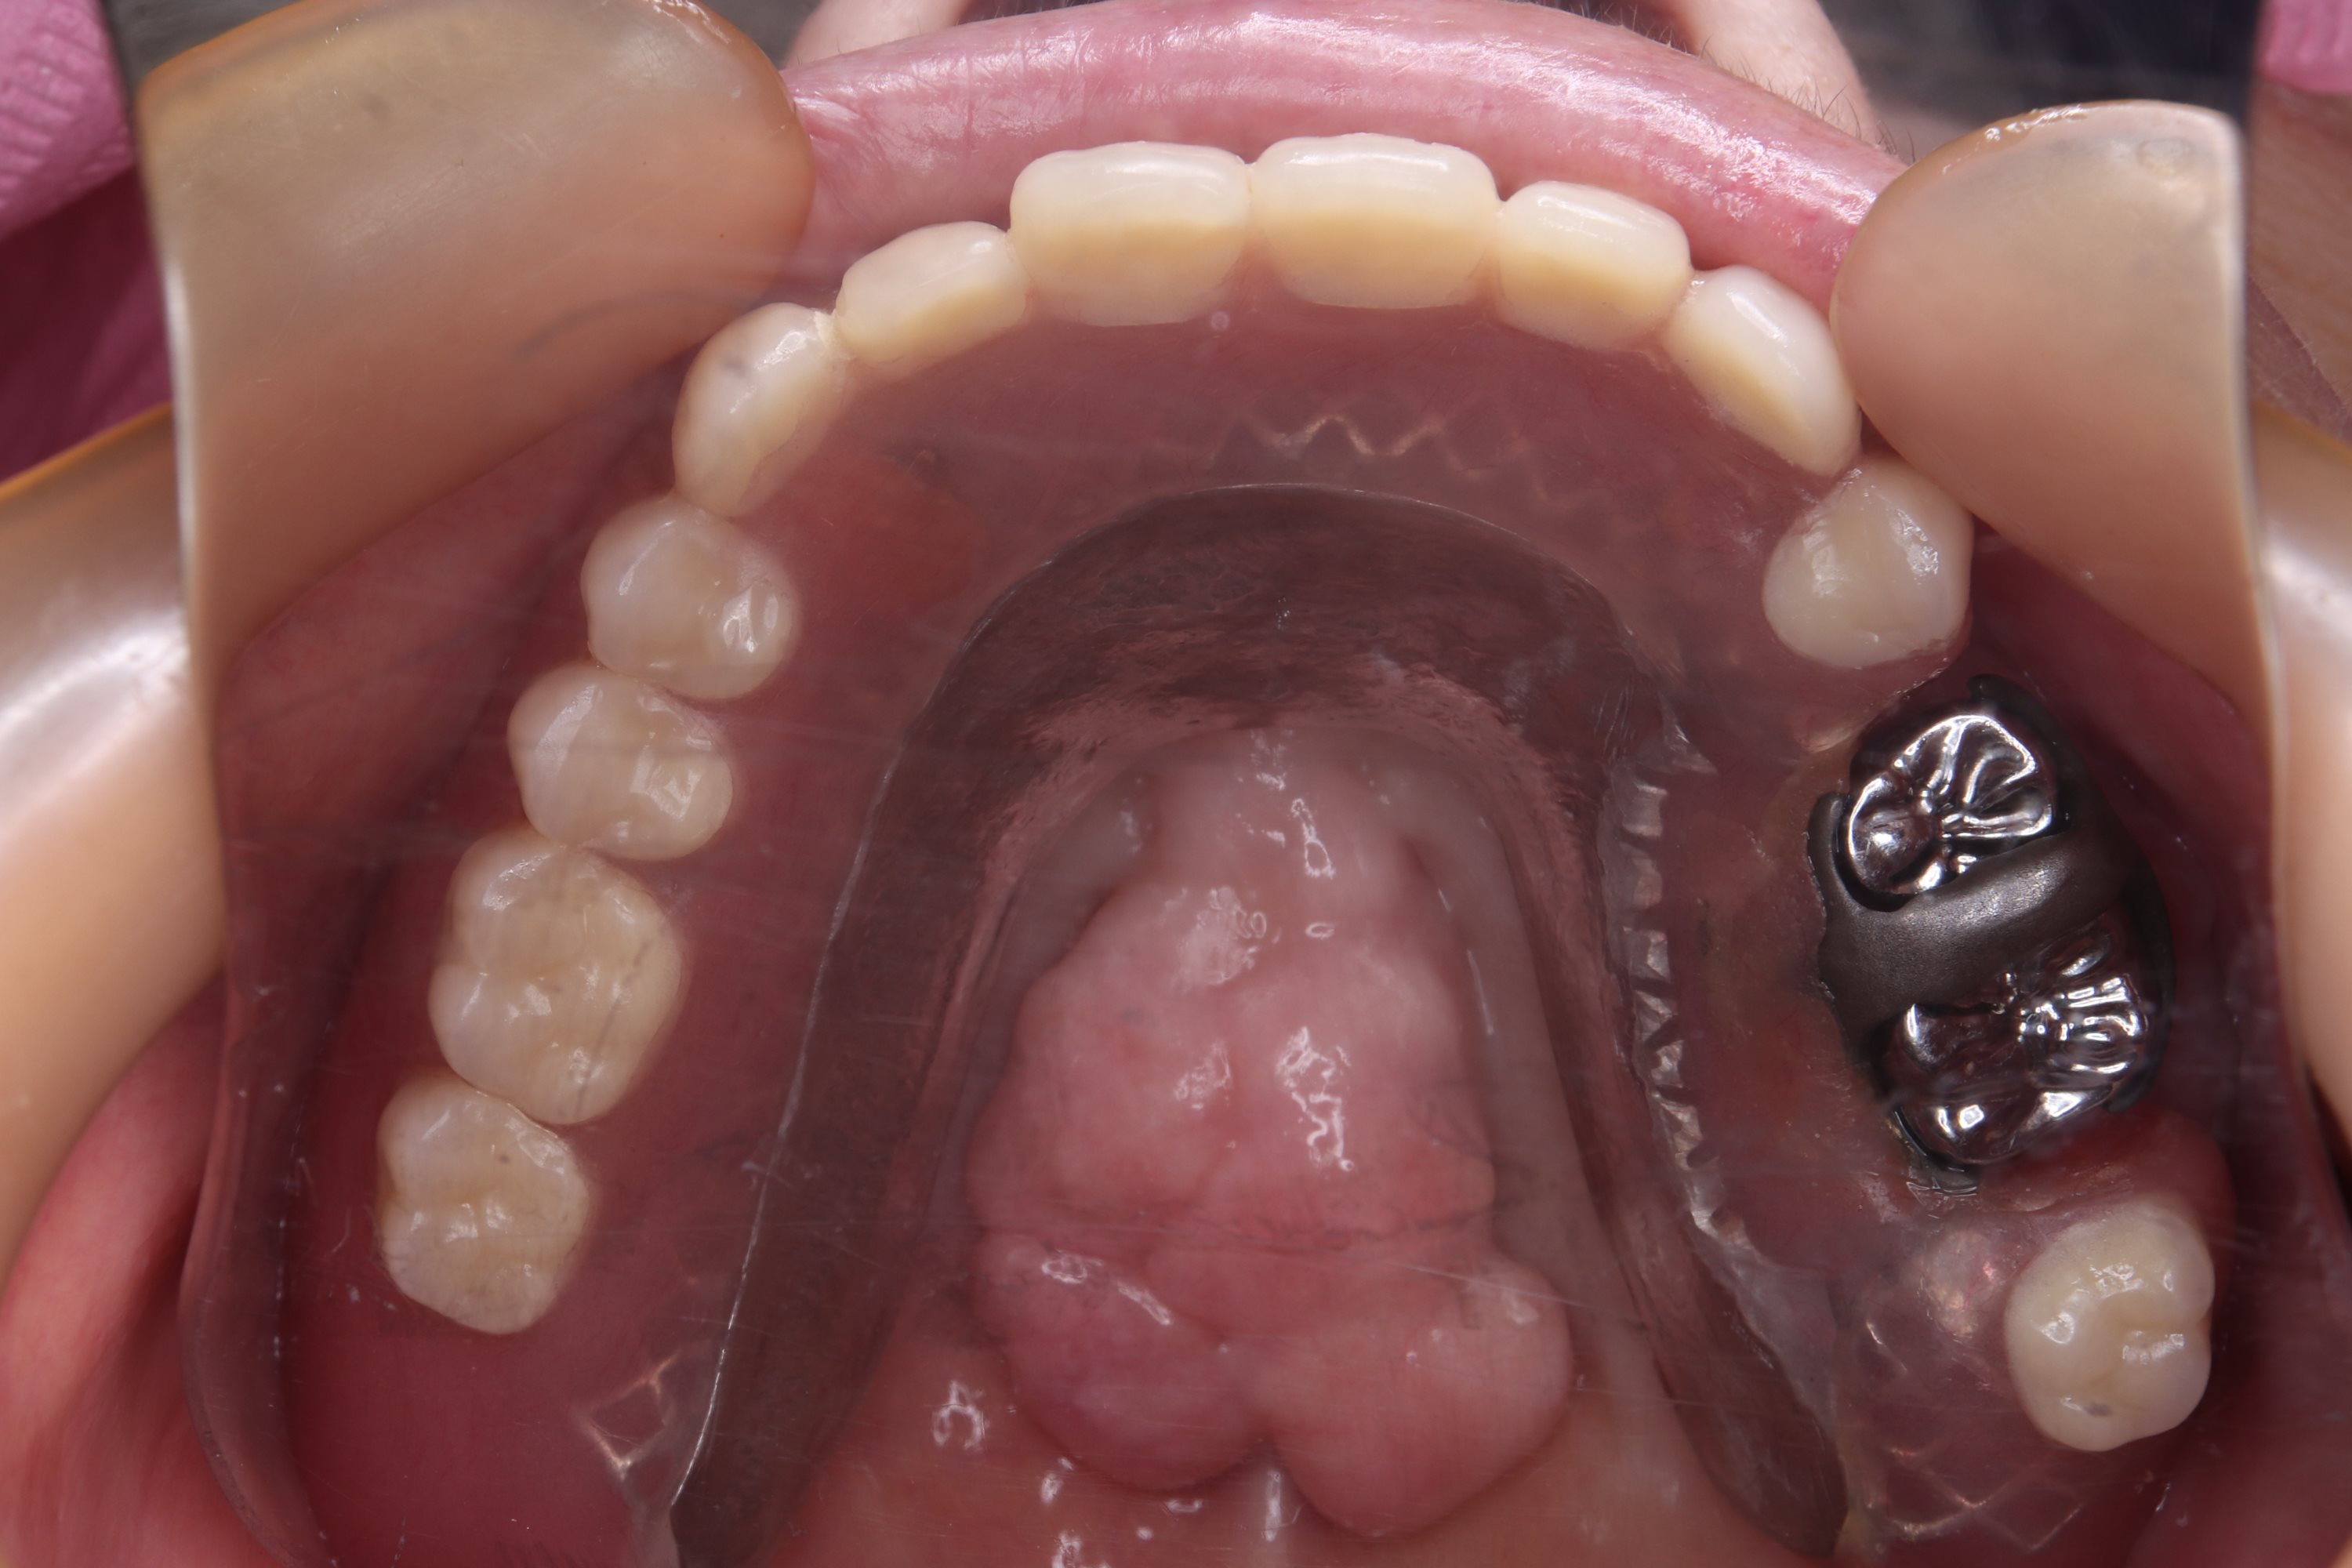

噛んでない銀歯

お口の中に入れ歯を入れて横から見てみると銀歯は、下の入れ歯と全然噛んでいません。

左奥銀歯から出血

奥の銀歯は、歯ぐきから出血しており、もうぷらぷらの状態です。